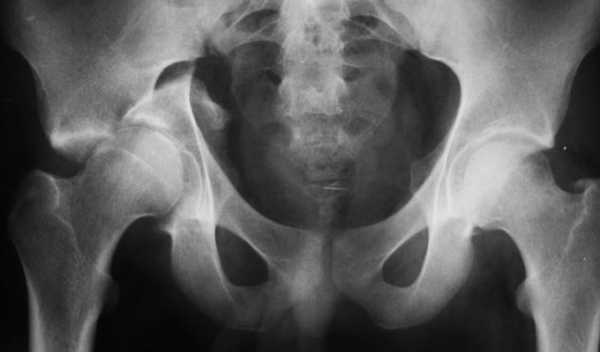

Точно диагностировать перелом дна вертлужной впадины можно при помощи рентгеновского аппарата. Он не только поможет подтвердить диагноз врача, но и даст наиболее полную информацию о существующей травме, поможет определить степень ее тяжести и назначить необходимое лечение.

Так как такой тип перелома очень сложно обнаружить, при наличии первых симптомов врачу необходимо провести рентгеновское исследование с использованием таких проекций:

- косая внутренняя и наружная проекция под углом 45 градусов;

- передняя и задняя тазовая;

- тазобедренная и бедренная переднезадняя проекция поврежденной стороны.

- трехпроекционная рентгенография таза и самого сустава;

Ставят диагноз основываясь на симптомах, данных рентгенологического и КТ исследований. Рентген делают в нескольких проекциях, снимок в прямой проекции оказывается малоинформативным для установления характера полученных повреждений.